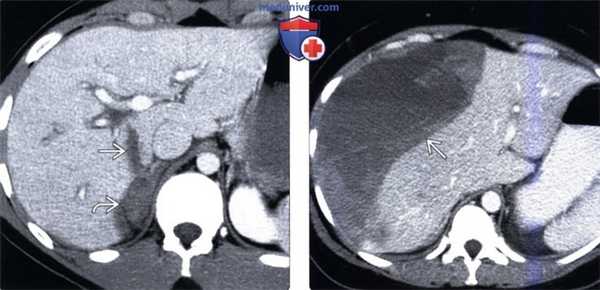

(Слева) На аксиальной КТ с контрастным усилением определяется линейный разрыв основания хвостатой доли, распространяющийся на внебрюшинное поле печени, приводящий к формированию забрюшинной гематомы (внутрибрюшное кровотечение в этой ситуации возникает реже).

(Справа) На аксиальной КТ с контрастным усилением визуализируется большая под капсульная гематома. Пациент недавно получил травму, но за медицинской помощью не обращался, самостоятельно принимал аспирин и ибупрофен. Изолированные подкапсульные гематомы при отсутствии интрапаренхиматозных кровоизлияний встречаются при травме нечасто.